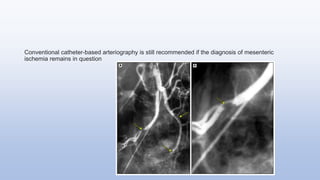

Conventional catheter-based arteriography is still recommended if the diagnosis of mesenteric

ischemia remains in question

Conventional catheter-based arteriographyis still recommended if the diagnosis of mesenteric ischemia remains in question